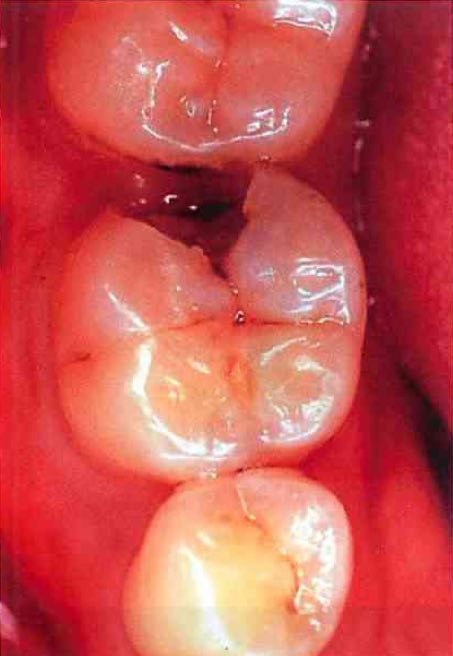

104B-43

45歳の男性。下顎左側第一大臼歯の咬合痛を主訴として来院した。感染根管治療を行うこととした。 クラウンと感染象牙質を除去した後の口腔内写真と感染根管治療開始日の口腔内写真とを別に示す。

感染根管治療開始前に行った処置の目的はどれか。2つ選べ。

隔壁形成写真 80

a 歯質の保存

b 咬合の維持

c 仮封の強化

d 審美性の回復

e 術野の汚染防止

正答 c, e

「仮封の強化」が答えづらいですが、 C4ぐらいのボロボロの歯冠に仮封剤を強引に使っても弱いのですぐ壊れてしまいます。すると根管が細菌に汚染されてしまいます。そこで、CRで強固な壁を作って(隔壁の形成)、ちょこっと仮封剤で蓋をしてあげることで封鎖性が強固になります。